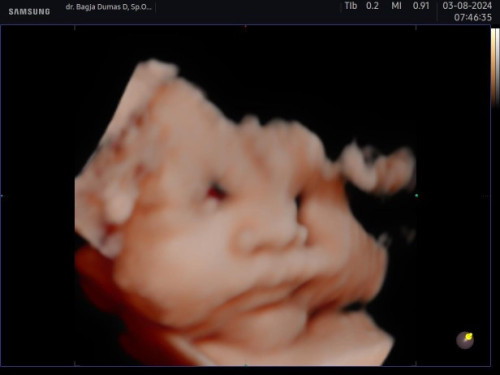

Hpl 21 september

Masih anteng debay

Baca lagitumpah2 pipinya ya ampunn